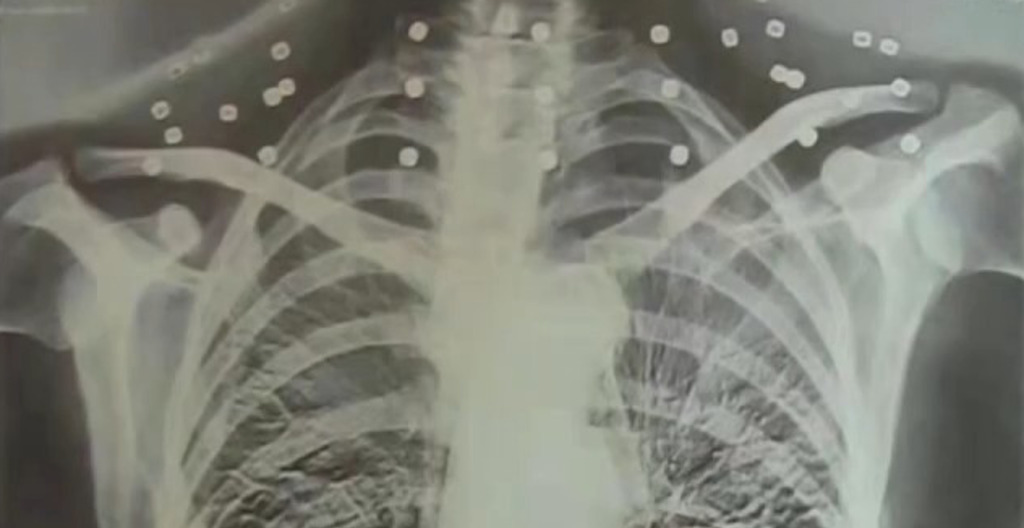

《央视》近日专访一名82岁老将吴以先,他秀出自己一张20年前做电脑断层扫描的影像,只见影像中靠近颈部的地方有许多放射呈现的圆点,吴以先透露,当时医生替他看报告做检查时,却跟他说“您要把项链拿下来才能拍断层照片做检查。”

当时疑惑的吴以先也向医生表示,自己从未有戴项链的习惯,仔细想一想后“怎么会有项链呢?医生你看会不会是弹片?”

从这里,带出了吴以先年轻时一段不平凡的往事。原来被体检医师误以为是项链的物体,竟是吴以先体内的33枚弹片,也是一条“摘不下来的项链。”